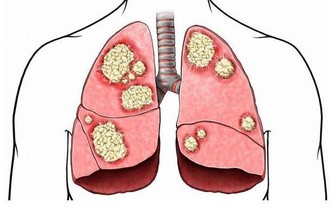

3. 去除痛風

小蘇打泡腳能消除痛風,尤其是上了年紀的人容易出現痛風,用2勺蘇打倒入溫水中,浸泡20分鐘,連續一周就能改善。